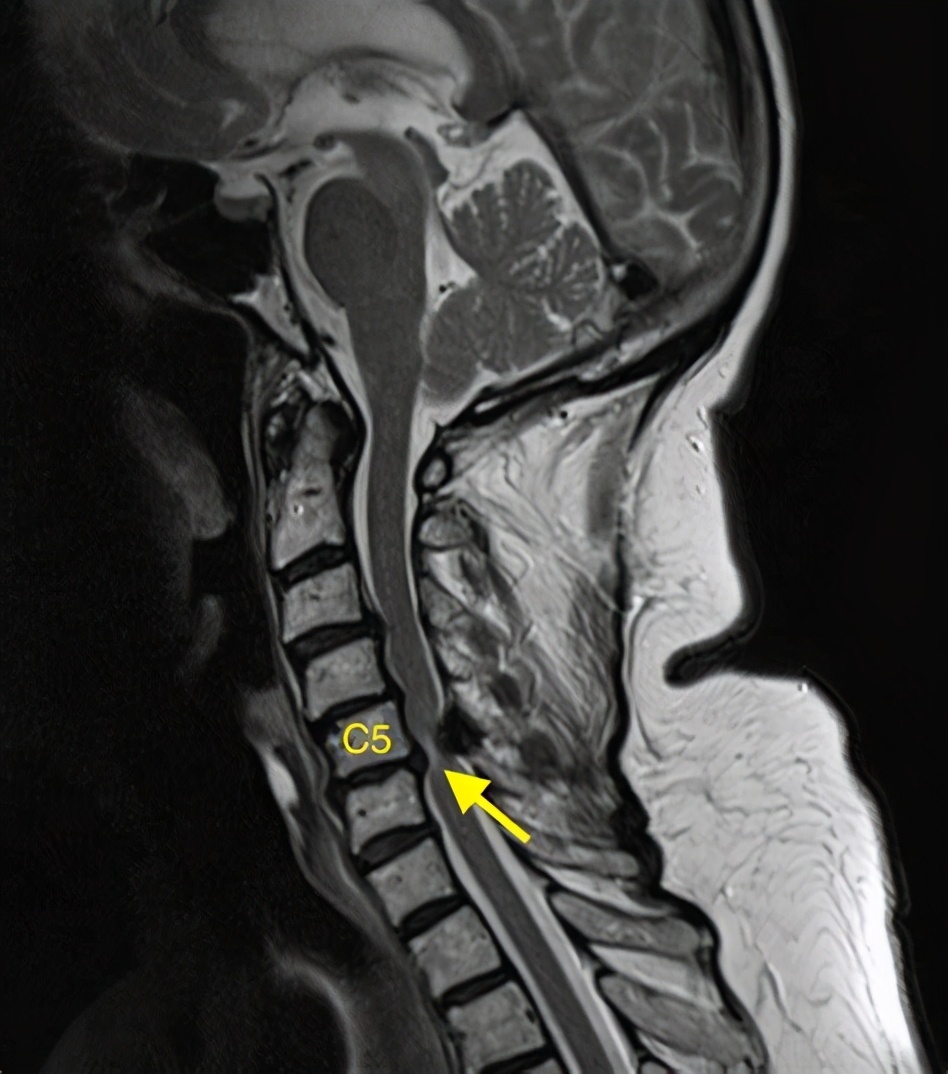

其实颈椎病是有很多类型的,这个患者就是脊髓型颈椎病已经挺严重的了,以前碰到过还跟他说千万不要摔倒,容易瘫痪,没想到冬天天冷路滑真的摔了一跤。

但是最为严重的也是临床中最值得注意的就是脊髓型颈椎病了。

如果脊髓受到压迫,遭受外伤或者其他*力暴**因素之后,就容易出现脊髓损伤,脊髓损伤,大家可能都听过,严重的时候会出现瘫痪。